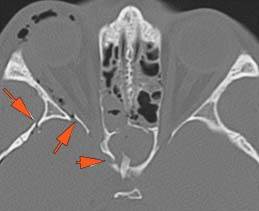

Midface Structures and Mandible

The pterygoid processes of the sphenoid bone are fractured.

There is bony injury or displacement of the body, angle, ramus, alveolar ridge, condylar coronoid process and parasymphyseal or symphyseal region of the mandible.